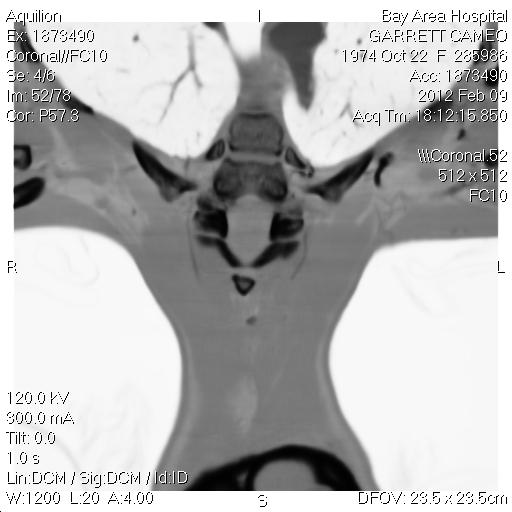

This view is of the 42nd photo in the coronal series, brain filter view. If you look right in the middle, there is a small black dot, and this is matching the same kind of result the implant in my tooth creates. The little bright circle things on my shoulders are from my hospital gown. So as you scroll down to see other views of the same photo, you will see how this artifact is picking up, and how it's near the plate in my neck, but is something separate from it. The black dot I'm referring to is in the center of the neck, a little bit higher than the R and L indicated right and left of my body, on the scan.

This is a lung filter, and I just used it to show how you could look at the same photo and see nothing, until you use a different contrast.

This is the bone view, which shows the bright white of the plate across my neck and then another bright white section which is from screws in my neck. You can see here that where the black dot is, has nothing to do with blood or a hole, as this is a part of my vertebrae. It's right next to the plate, but it's different, and I believe it indicates implant that is separate from the plate. Also, there are two screws in addition to the plate in my neck, but there is only this one dot. I can put up more of the dental implant photos to show the difference between the implant there and the metal filling as well. I also have some interesting images of the one ear that has an implant in it and it's different from my other ear. If it looks small, that's why they call them "microchips". In this view, actually the screws are above the plate in the photo, because it's a transitioning photo. They are actually below the plate, but this still captures what is inbetween. I'll put more up tomorrow.